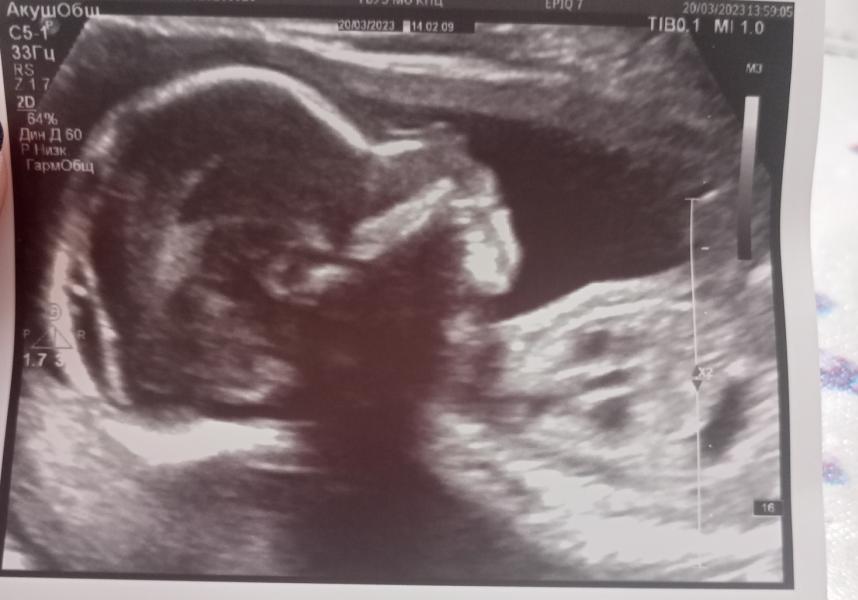

Девочки)) вести с ,,полей,, вчера был второй скрининг, теперь точно девочка)) вторая принцесса)) вес 365 гр, по малышке 20.5🤗🤭